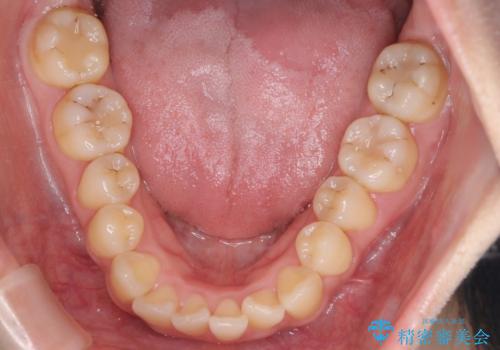

- 前歯のがたつきを治したいという主訴で来院されました。1年後に転勤の可能性があり短期間での治療を希望されました。今回は非抜歯の治療を計画し、IPRと拡大をし、前歯の叢生を改善しました。

前歯のがたつきを治しながら2番の反対咬合も改善させました。短期間で終了し満足していただけました。